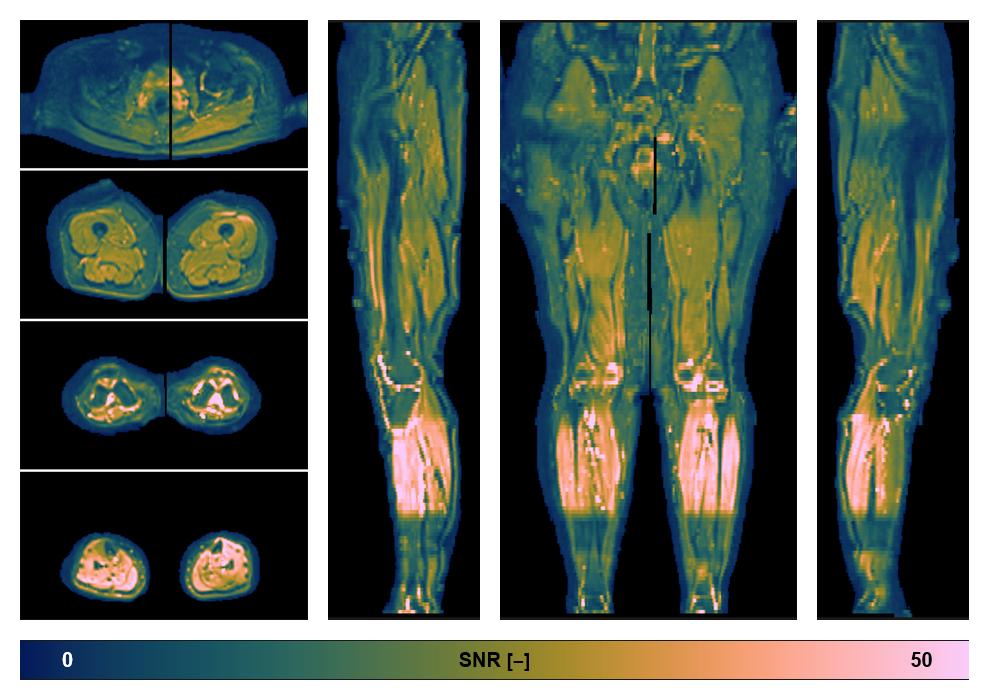

• SNR distribution

The SNR distribution of the dixon data.

• SNR of the unweighted image

SNR distribution of the unweighted diffusion data.